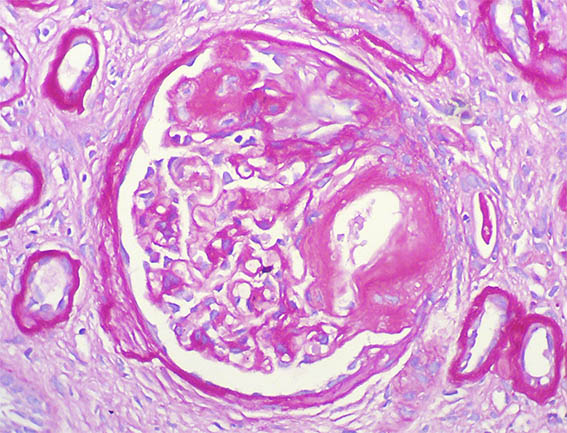

Figura 4. H&E, X400.